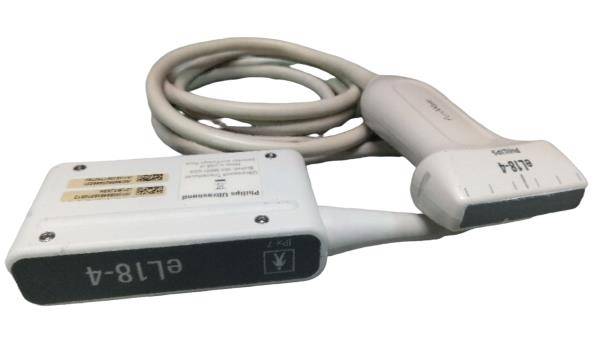

Toshiba Probes

Toshiba Probes

DIAGNOSTIC ULTRASOUND MACHINES FOR SALE